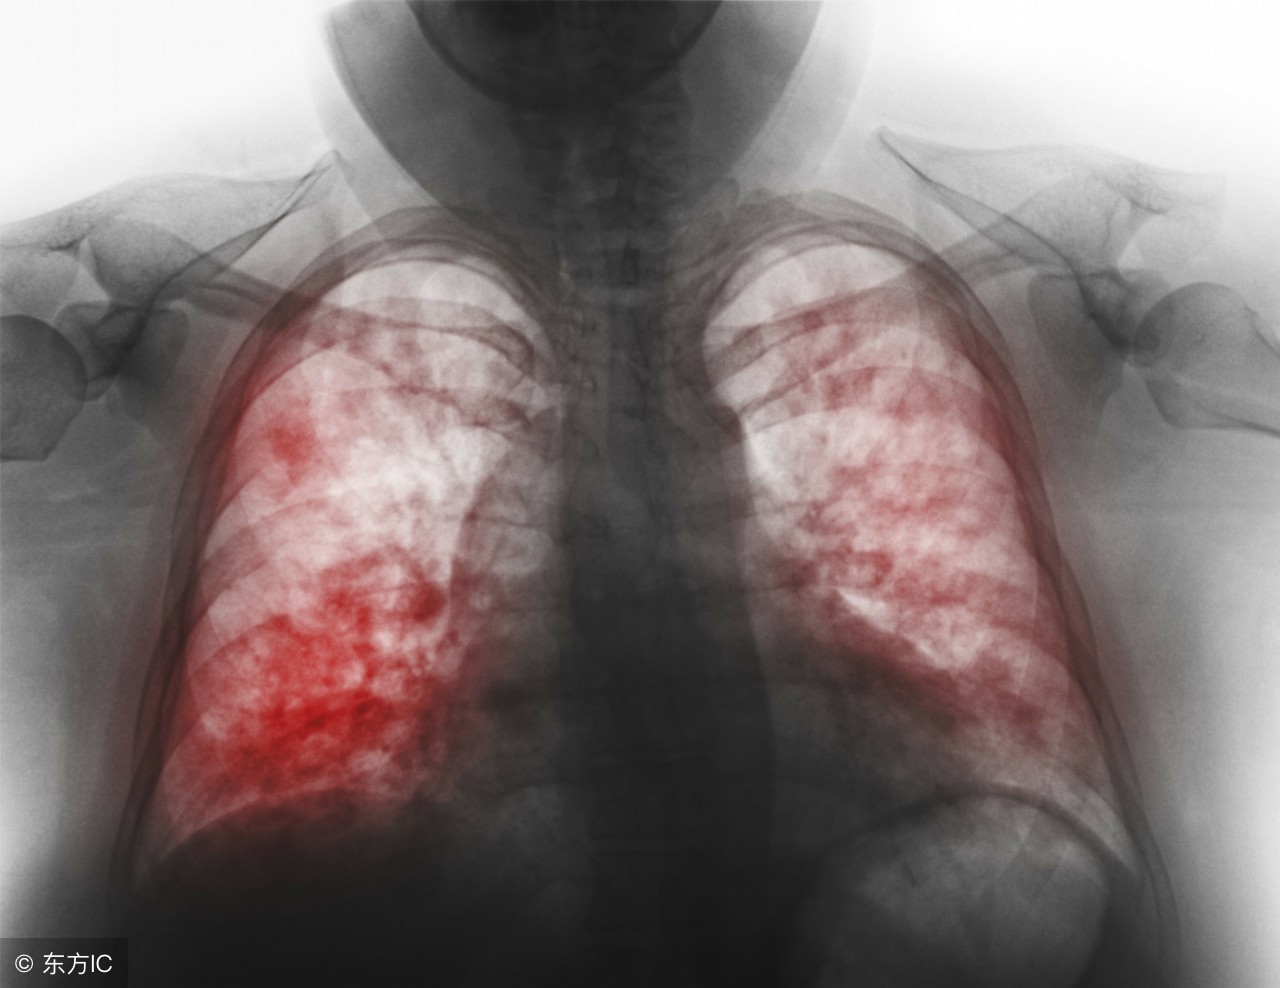

2.影像学检查 影像学检查是诊断肺炎的重要指标,也是判断重症肺炎的重要指标之一。肺炎的影像学表现:片状、斑片状浸润性阴影或间质性改变,伴或不伴胸腔积液。影像学出现多叶或双肺改变、或入院48h内病变扩大≥50%,提示为重症肺炎。由于表现具有多样性,特异性较差。但影像改变仍对相关病原菌具有一定的提示意义(见表1)。

⑺ X线胸片显示双侧或多肺叶浸润影,或入院48小时内肺部浸润影扩大≥50%;